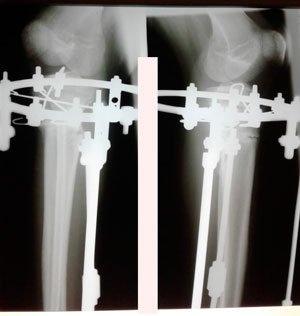

Исходник - 15 лет. Павлодар.

Дата операции - 15.06.2019г.

Дата снятия аппаратов - 20.08.2019.

Срок сращения - 65 дней.